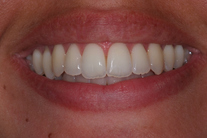

Tandreglering 1

Ung kvinna som tidigare haft tandreglering. Upplever inte att tänderna står i en fin tandbåge. 11 månaders behandling med genomskinliga Invisalignskenor resulterade i ett fint leende.